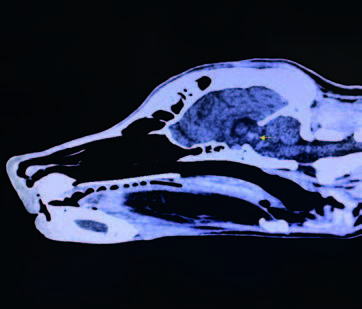

This case study involves a 5-monthsold, intact male Golden Retriever dog presented with tetraparesis, seizure and comatose by a car accident 5 days ago. Physical examination presented unconsciousness, tetraparesis, tachypnea, right temporomandibular joint (TMJ) luxated and crepitus of left humerus. Neurological examination was localized to cerebral cortex and brain stem lesions. The Modified Glasgow Coma Scale (MGCS) was 3. Laboratory tests revealed anemia of 23.1% (reference range, 35-45%), leukocytosis of 19.09 x 103/μL (reference range, 5-14.1 x 103/μL). Radiography was presented to skull fracture, lung hemorrhage (Figure 1) and left humerus fracture (Figure 2).